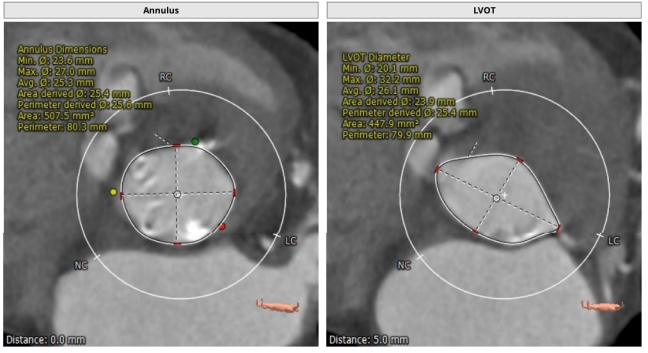

瓣环平均直径:25.6 mm,左室流出道平均直径:25.4 mm,升主动脉未见明显扩张,心脏角度:51°

瓣环平均直径:21.9 mm,左室流出道平均直径:21.6 mm,钙化积分:865.9 mm³